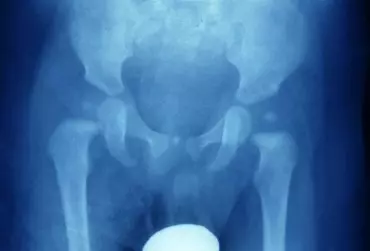

FirstBIKE jako innowacyjna metoda terapeutyczna w dysplazji stawów biodrowych u dzieci

Powszechny problem u dzieci i niemowląt stanowią zaburzenia w funkcjonowaniu stawów biodrowych. Do tego zjawiska przyczynia się m.in. fizjologiczna niedojrzałość elementów stawu, w wyniku której bardzo łatwo o zaburzenie prawidłowej gry stawowej czyli nieodpowiednie przemieszczanie struktur względem siebie.